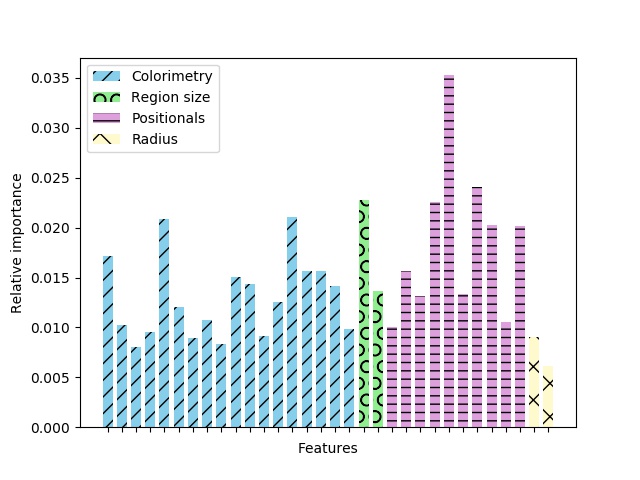

To study the task at hand, we analyse the importance of each feature used to distinguish nail and toe regions. In Fig. 9, we can see the importance of the features in the gradient boosting classifier. Such feature importance is averaged over the trees that conform the gradient boosting ensemble. In individual trees, it is a measure of how well each variable splits the data at a specific node Hastie et al. (2009).

We observe that the most informative feature of the classifier is, however, a positional feature: the distance between a super-pixel centroid and the center of the estimated nail circle. Again in Fig. 9, we observe that the difference between this feature importance and the other ones is enormous in relative terms. This is because the regions identified as nail are the ones closer to the circle, and the distant ones can be straightforwardly discarded.

The colorimetry represents the larger group of features used by the training models. The two most informative ones in this group are the mean and the standard deviation of the a channel from the CIELAB color space.

Other features that give important information are the super-pixel area, and the distances in the Y axis to the nail circle and to the lowest skin pixel.

Nail and skin can not be segmented using only color or local information. The pixel-wise colors of human nails are indistinguishable from those belonging to toes (see Sect. 2). This is specially important when dealing with different skin shades or illumination conditions. We can not, however, disregard photometric information (see Fig. 9).